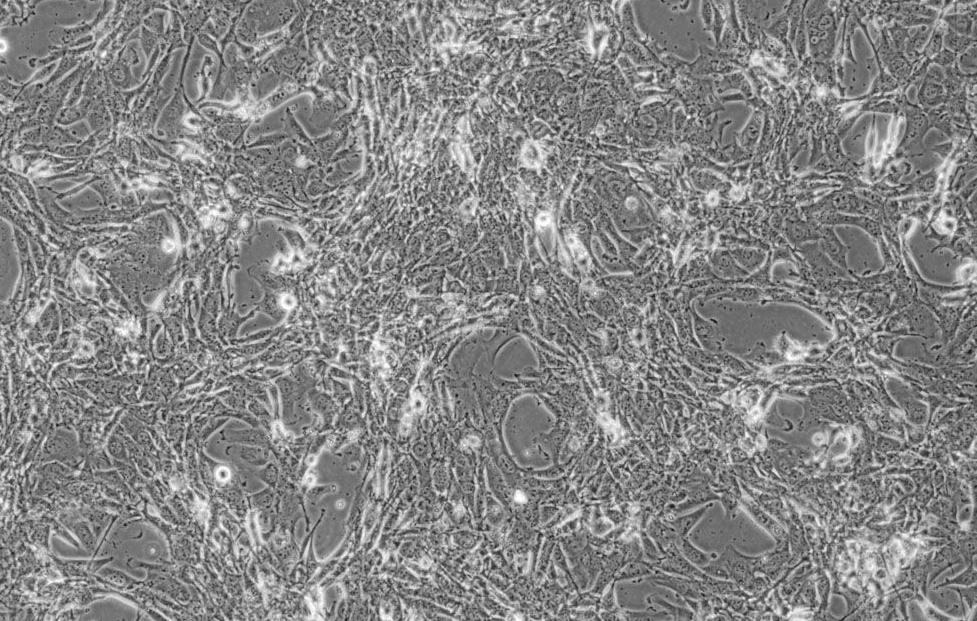

形態(tài) |

上皮細(xì)胞樣 |

生長(zhǎng)特征 |

貼壁生長(zhǎng) |